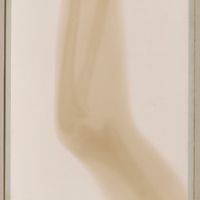

0087 - Page 47 - 29 avril - Enfant de 12 ans. - Coude très tuméfié, subluxation traumatique avec décollements épiphysaires0087 - Page 47 - 29 avril - Enfant de 12 ans. - Coude très tuméfié, subluxation traumatique avec décollements épiphysaires

0091 - Page 49 - [traumatisme du coude]0091 - Page 49 - [traumatisme du coude]

0095 - Page 52 - [Os du bras. Myosite ossifiante progressive]0095 - Page 52 - [Os du bras. Myosite ossifiante progressive]

0111 - Page 60 - n° 60 [malformation de la main]0111 - Page 60 - n° 60 [malformation de la main]

0117 - Page 61 - 61 [coude]0117 - Page 61 - 61 [coude]

0123 - Page 65 - n° 65 [coude]0123 - Page 65 - n° 65 [coude]